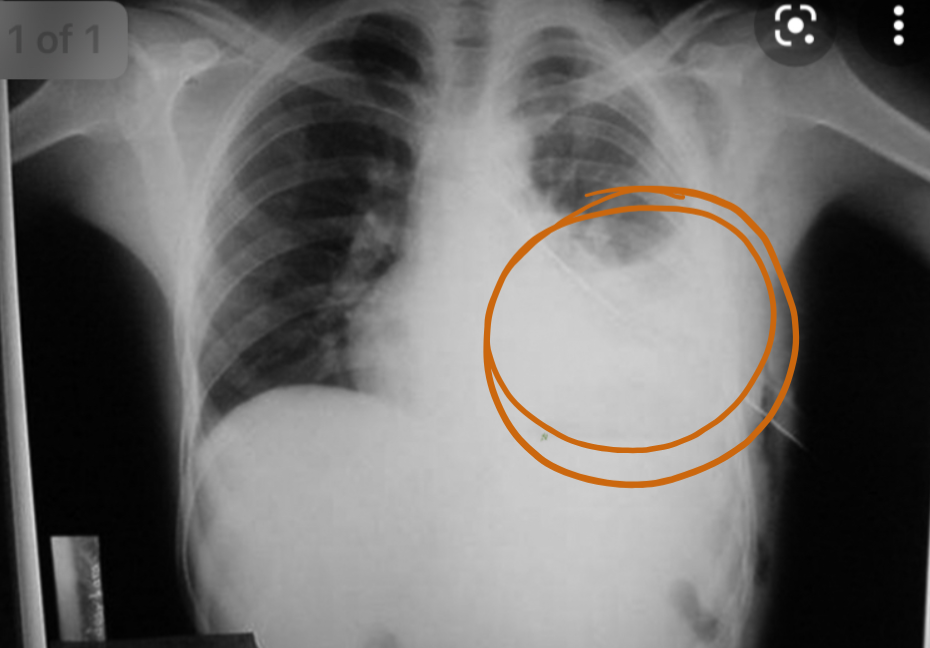

X Ray of pneumothorax.

1. What abnormalities do you see? Answer:

1. lucency of left hemithorax

2. absent broncho-vascular markings

3. shifted trachea to the right + mediastinum Distended vein Asymetrical chest Mvmt.

Q1- modality and what is your finding? Chest x-ray, Left lung hemothorax

Q2- signs on examination? Dullness on percussion, Flat vein

Asymmetrical chest movement in inspection

management?  Chest tube in 5th intercostal space, Fluid resuscitation, Thoracotomy (This is the only question that was not from question bank)